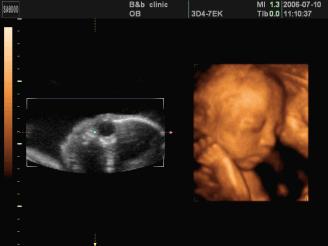

是立体动态显示的彩色多普勒超声诊断仪,可以进行胎儿头面部立体成像,可显示眼、鼻、口、下颌等态势,协助医生直接对胎儿先天畸形进行诊断,价格比普通彩超价格贵。

四维彩超能够对胎儿进行动态、立体超声检查,显示胎儿的面部、各器官的发育情况,甚至胎儿在母体里的态势也可以视察到;对胎儿畸形,如唇裂、腭裂、骨骼发育异常等能早期诊断。另外还能制作成光盘,让宝宝拥有最完整的0岁相册,留下永久的记忆。